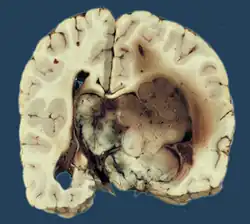

Das Plexus-choroideus-Papillom, kurz Plexuspapillom, ist ein seltener gutartiger Hirntumor, der von der Deckschicht (Epithel) des Adergeflechts (Plexus choroideus) ausgeht. Plexuspapillome sind seltene Tumoren, die nur etwa 0,5 % aller Hirntumoren ausmachen. Ganz überwiegend sind Kinder und Jugendliche betroffen.[1] Das Plexuspapillom führt zu einer Erhöhung des Hirndrucks mit Kopfschmerz, Übelkeit und Erbrechen. Die Diagnose wird durch eine Magnetresonanztomographie gestellt. Nach operativer Entfernung ist die Heilungsaussicht sehr günstig, weswegen der Tumor nach der WHO-Klassifikation der Tumoren des zentralen Nervensystems als Grad 1 eingestuft wird.

Histologie

Das feingewebliche Bild ähnelt mit Ausbildung papillärer Strukturen weitgehend dem des normalen Plexus choroideus. Tumoren, die atypische histologische Eigenschaften (insbesondere eine erhöhte mitotische Aktivität) aufweisen, werden als atypisches Plexuspapillom bezeichnet.[5]

Bildgebung

In der Kernspintomographie stellen sich Plexuspapillome recht charakteristisch als intensiv homogen Kontrastmittel aufnehmende, in den Hirnventrikeln gelegene Masse mit blumenkohlartiger Form dar. Bei Kindern und Jugendlichen sind vor allem die Seitenventrikel betroffen, bei Erwachsenen gleichermaßen der vierte Ventrikel. Selten können Plexuspapillome auch im dritten Ventrikel oder ganz außerhalb des Ventrikelsystems liegen.[1][8]